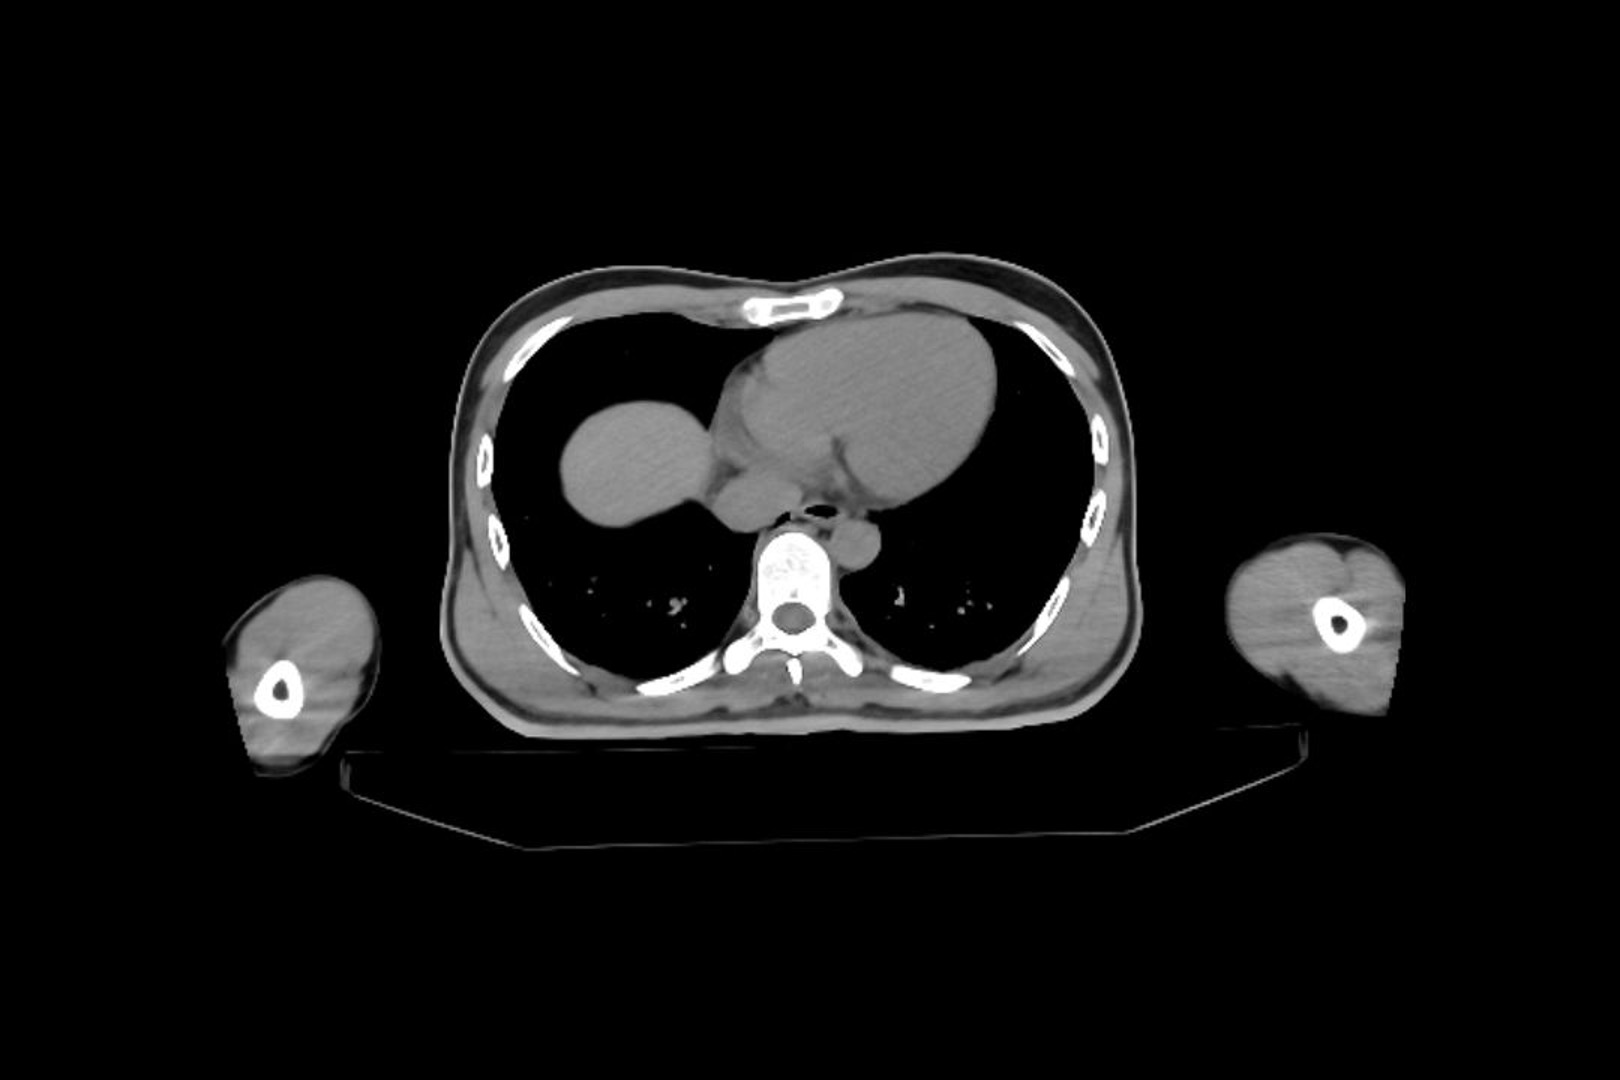

交通外傷の20歳代男性

軽自動車乗車中,右折時に対向車から衝突される.腹部にシートベルト痕あり.

意識清明.心拍数88回/分,血圧110/68 mmHg,SpO

2

100%(room air),右側腹部を中心に圧痛あり.

明らかな貧血所見なし.

Q:腹部単純CT(図1)に認められる画像所見は?

図1 腹部単純CT横断像